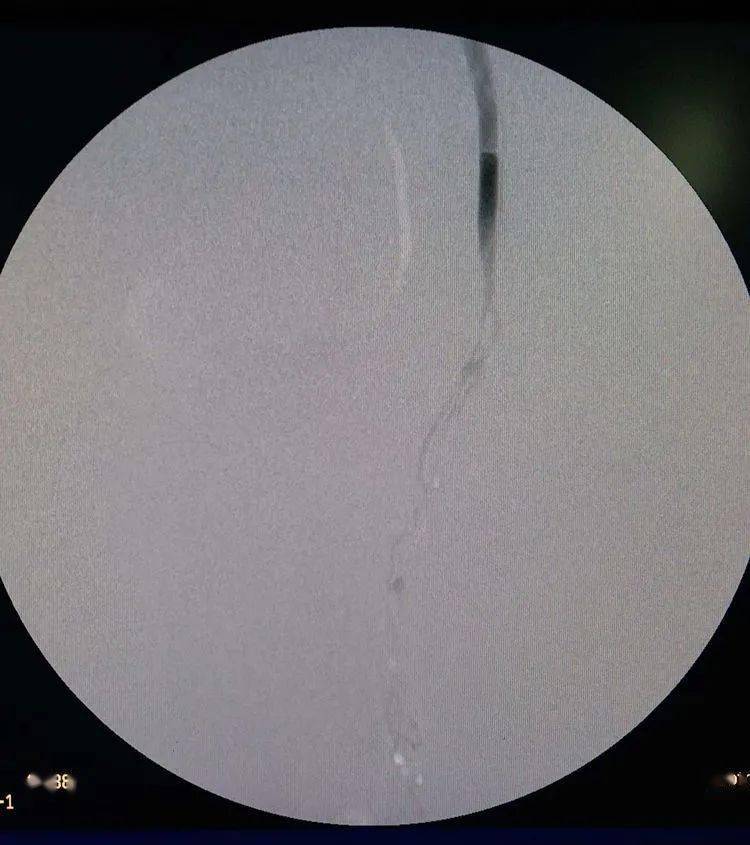

正文 2019-6-12 来自 iphone客户端 关注 无精子症:需要行输精管造影

手术中同时做输精管造影检查,显示输精管道梗阻部位(2020.5.

输精管造影的注意事项

输精管造影检查前注意问题